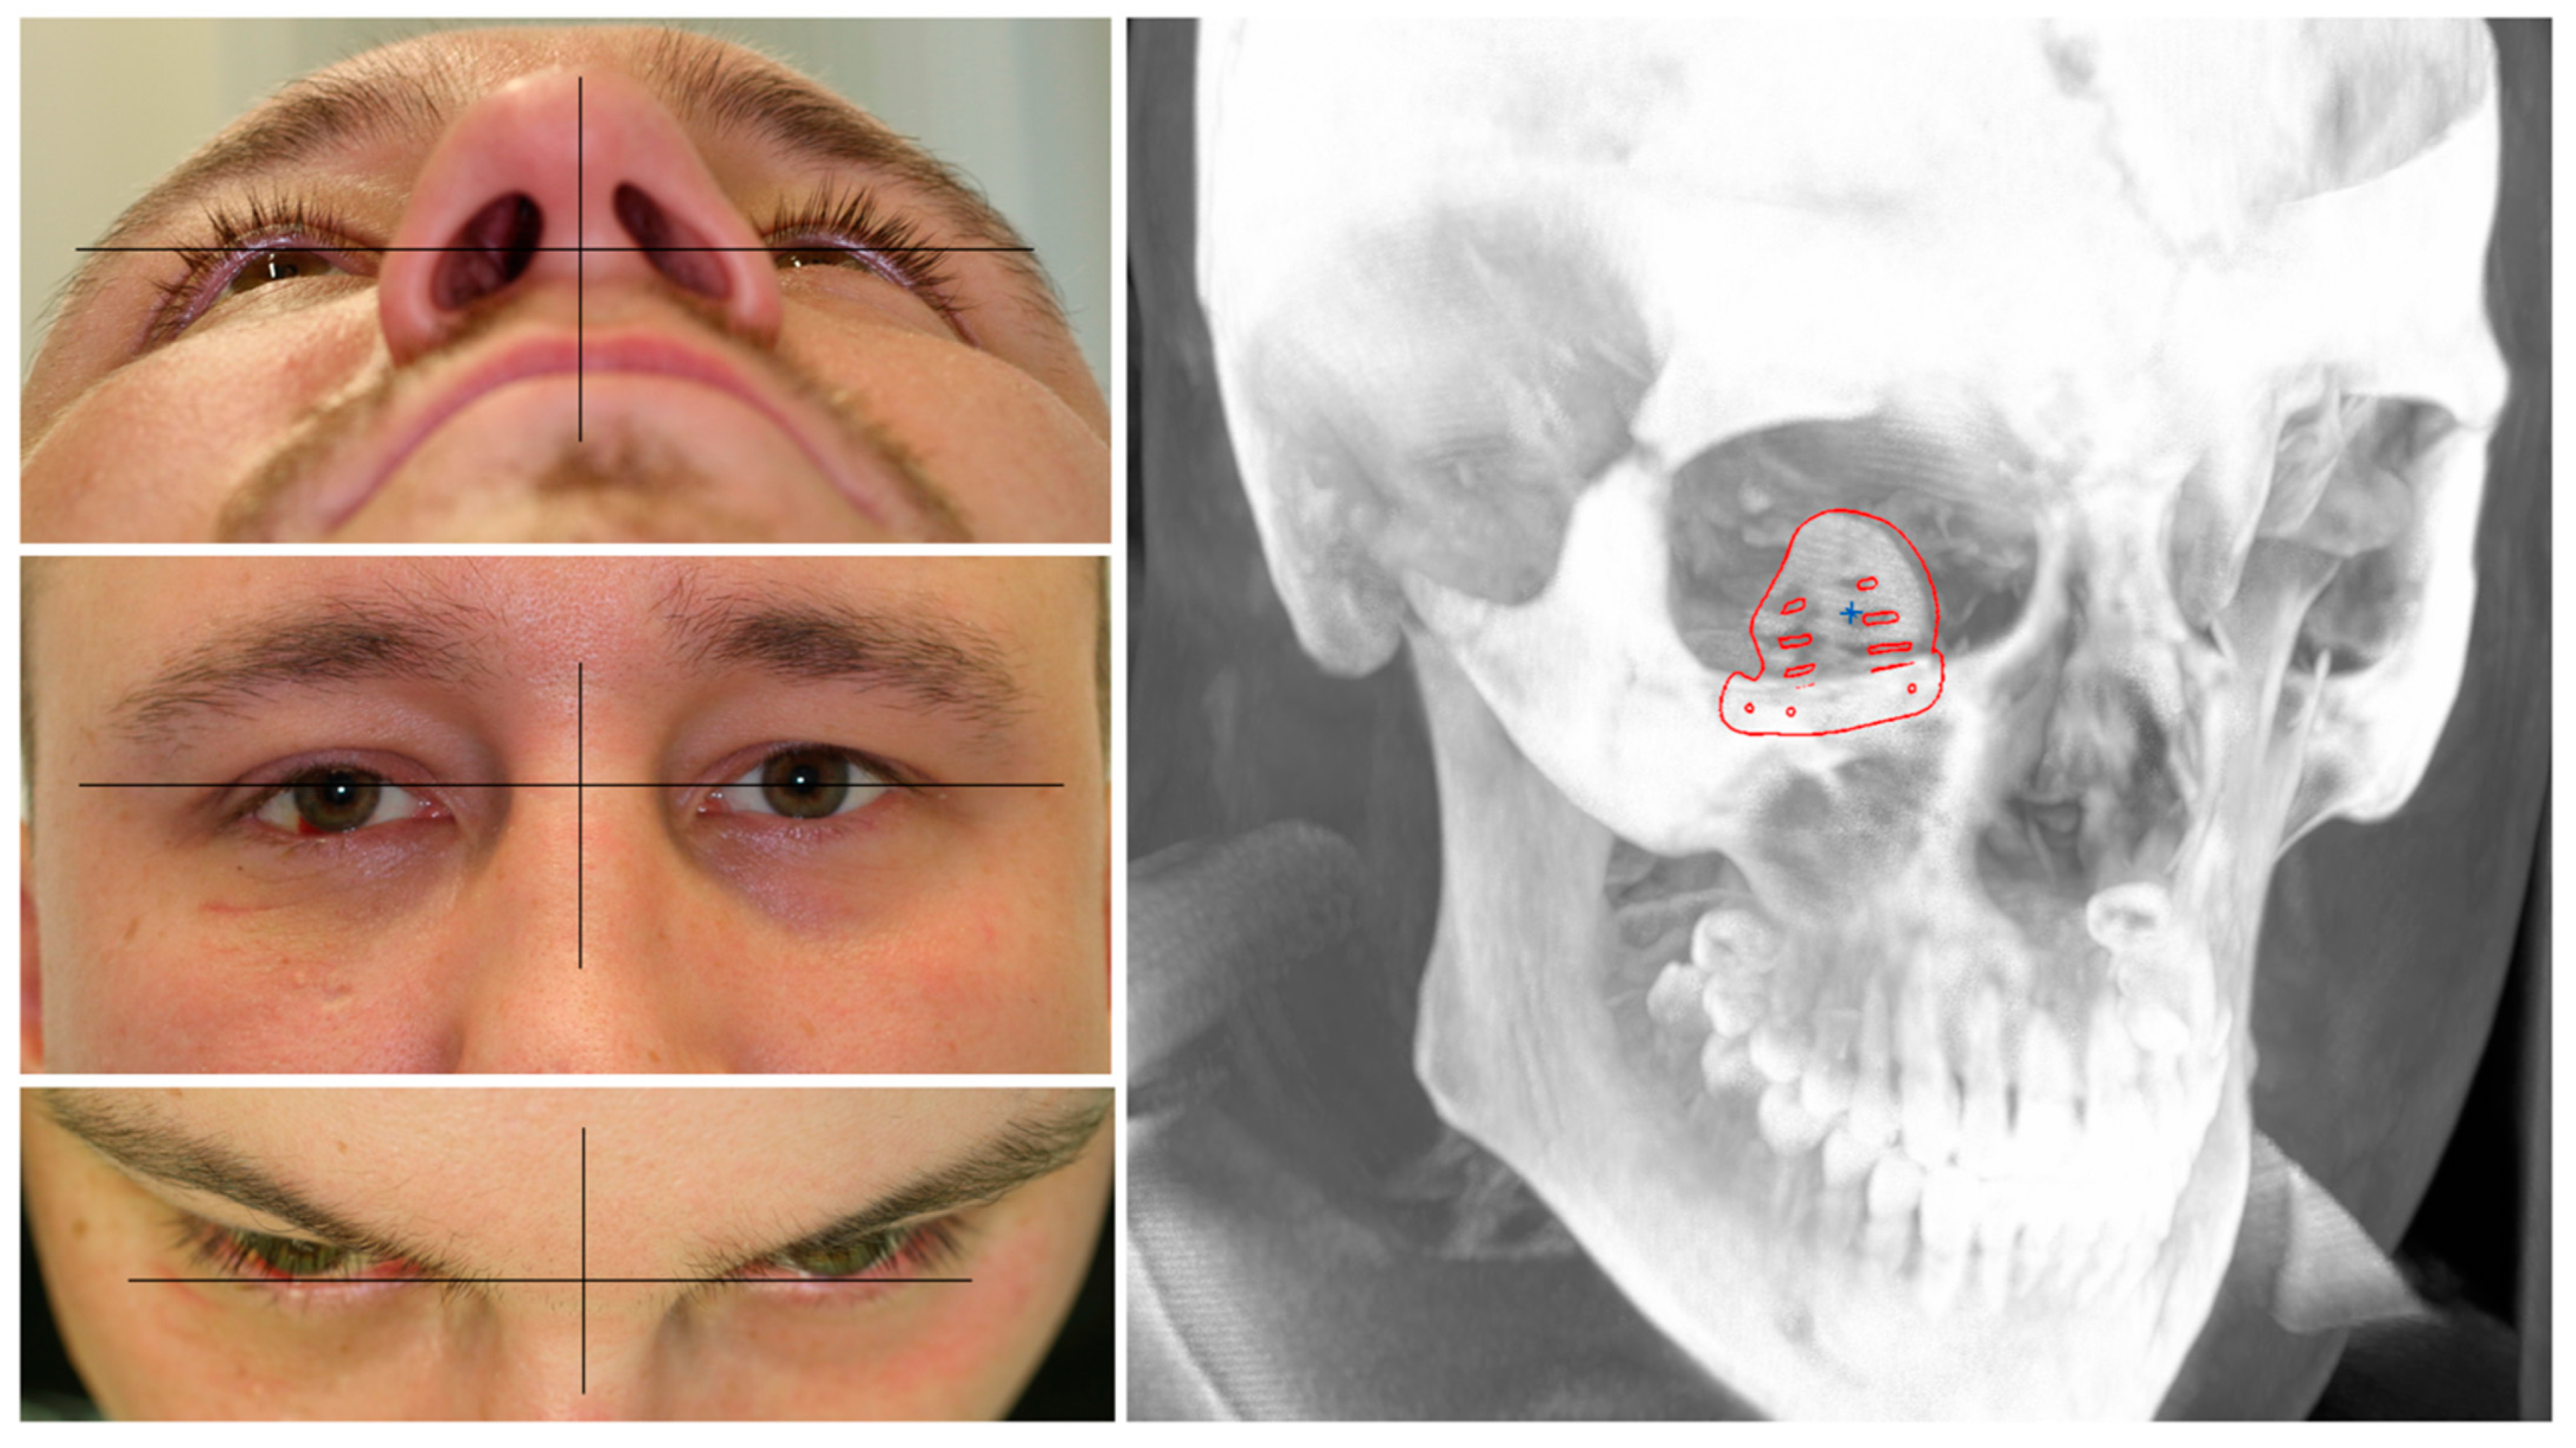

2.1. Case Demonstration

2.4. Surgical Procedure and Clinical Outcome